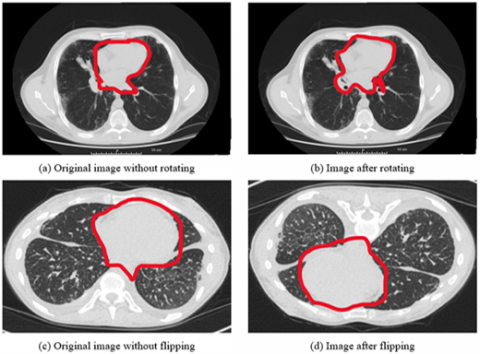

Lung cancer is detected and treated with the use of imaging methods such as multidetector X-ray computed tomography (MDCT) [5]. If you have a CT scanning today, you will get a large amount of information. Performing all of this data segmentation and analysis by hand is difficult and time-consuming. It makes the work of the radiologist more complicated and time-consuming. Glancing at a large number of images can increase the likelihood of missing essential clinical criteria, such as abnormalities, was shown in the Figure 1.

Figure 1. Showing the limitations of the normal image-based segmentation

Figure 4. Showing the data augmentation on LuNa-16 dataset images before and after segmentation

Although the orientation of the microscope images does not vary, the sharpness of the target cell varies depending on where the microscope's focus plane is located. As consequence, by rotating, inverting, and filtering the image, we were able to extract additional information from it.

This was done in order to ensure that the number of better images for each of the three illness groups was equal for all three disease groups. As a consequence, there were twice as many images included in the final version as there were in the initial version. With a Gaussian filter with a standard deviation of three pixels, the images were enhanced, as was the edges with a convolutional edge enhancement filter that had a central weight of 5.4 and an 8-surrounding weight of 55% and improved the edges' appearance was shown in the Figure 4.